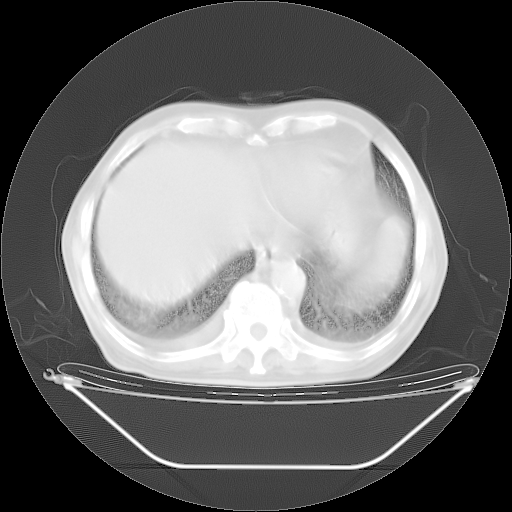

今天复查肺部CT,发现双肺广泛磨玻璃样改变。所以我把3月19日和5月9日相隔50天的肺部CT上传。请大家会诊。

5月9日肺部CT(在4月27日齐鲁医院肺部CT描述部分肺组织磨玻璃样改变,12天后肺组织广泛磨玻璃样改变)

2009年5月9日肺部CT